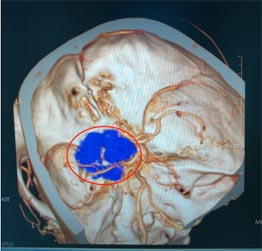

广东三九脑科医院的头颅MR检查显示:左侧蝶骨嵴占位性病变,大小约3.5cm×2.8cm×3.6cm,考虑脑膜瘤;头颅CTA提示:病灶内钙化灶,血供较丰富,病灶部分包绕左侧颈内动脉,压迫左侧大脑中动脉水平段向后移位。

▲术前CTA